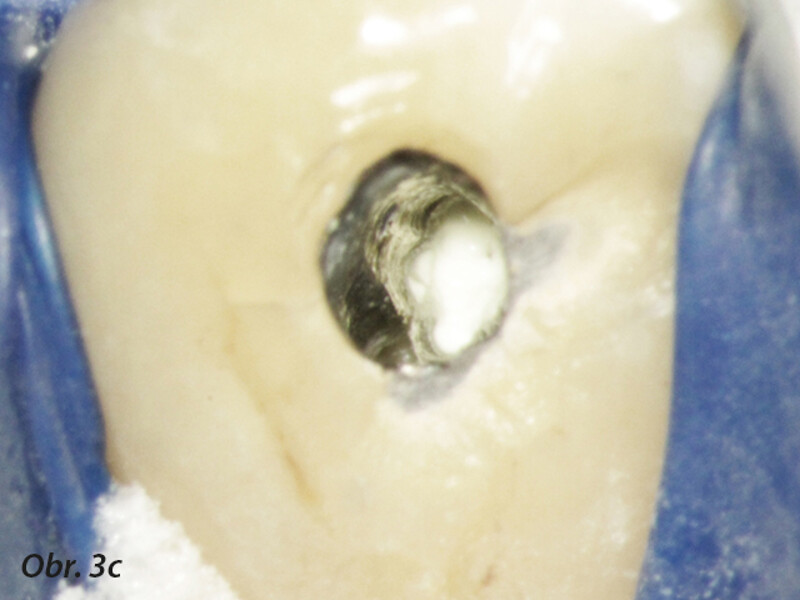

Aplikace MTA s použitím Produit Dentaires (PD) MAP System